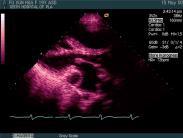

三尖瓣下移畸形

• 三尖瓣下移畸形

628健康網為您分享有關三尖瓣下移畸形的癥狀,三尖瓣下移畸形的治療方法,三尖瓣下移畸形的預防知識,三尖瓣下移畸形的癥狀...